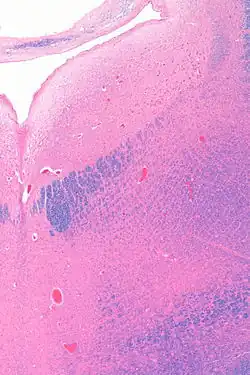

Micrograph showing the locus coeruleus (upper-right of image) in an axial section of the pons. The fourth ventricle (quasi-triangular white area) is in the upper-left of the image. The midline is seen on the left. The large white area in the upper-left corner is where the cerebellum would be. HE-LFB stain.

Micrograph showing the locus coeruleus. HE-LFB stain

The locus coeruleus (LC) is located in the posterior area of the rostral pons in the lateral floor of the fourth ventricle. It is composed of mostly medium-size neurons. Melanin granules inside the neurons contribute to its blue colour. Thus, it is also known as the blue nucleus, or the nucleus pigmentosus pontis (heavily pigmented pontine nucleus).[5] The neuromelanin is formed by the polymerization of norepinephrine and is analogous to the black dopamine-based neuromelanin in the substantia nigra.